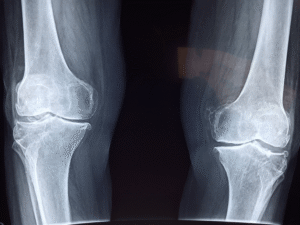

Dr. Suhail Hussain and the Royal Osteoporosis Society explain that bone strength is often inherited — your DNA affects bone density, calcium absorption, and bone structure. If a parent broke a hip, you’re more likely to experience fractures too. Bone strength also declines with age, especially after 30 or menopause in women.

If you’re concerned, a bone density (DEXA) scan is a quick, painless way to assess your bone health. Being proactive with diet and exercise is your best defense — not relying on luck or spiritual protection.